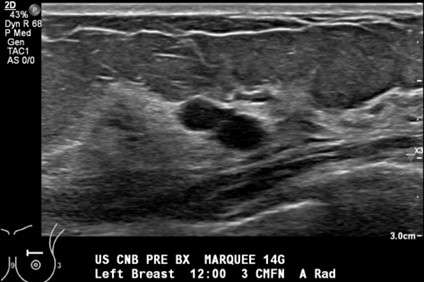

Technologist confirms the lesion is still visualized and saves a pre-procedure image (Figure 1).

Figure 1. Grayscale sonogram shows two adjacent well-circumscribed, anechoic cysts at 12:00, 3 cm from the nipple.- Radiologist performs time out and confirms patient identity, procedure, and side.